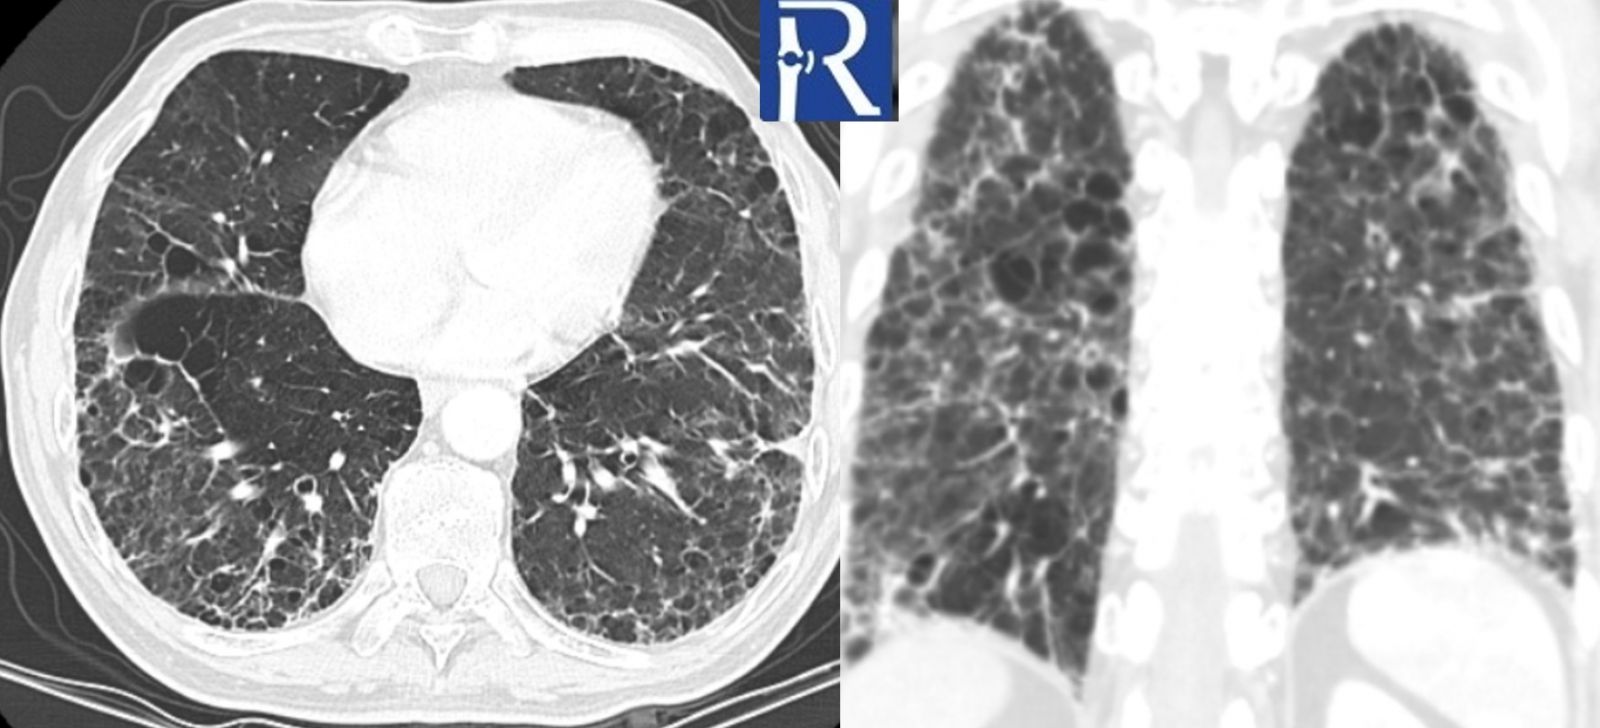

Thoracic CT demonstrates widespread subpleural thickening, reticular opacities, and a mild honeycombing pattern in both lungs.

Inflammatory myopathies frequently coexist with interstitial lung disease (ILD), and in some cases, ILD may dominate the clinical picture. A strong association has been reported between myositis-specific antibody (MSA) positivity and pulmonary involvement. The presence of ILD in patients with myositis is associated with increased morbidity and mortality